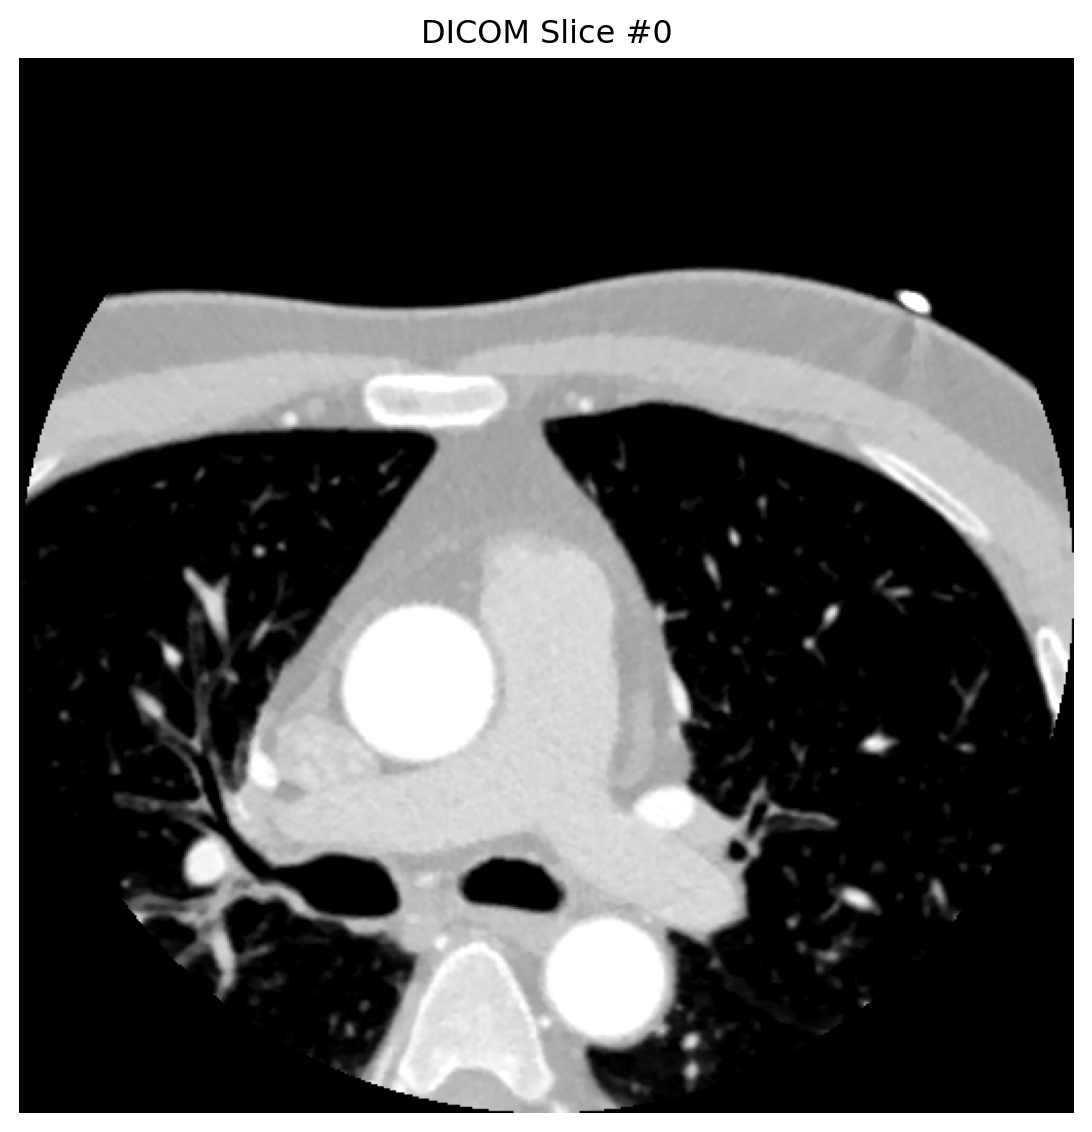

# 分析多个代表性切片

for slice_idx in [0, 4, 8]:

dataset = analyze_dicom_slice(slice_idx)